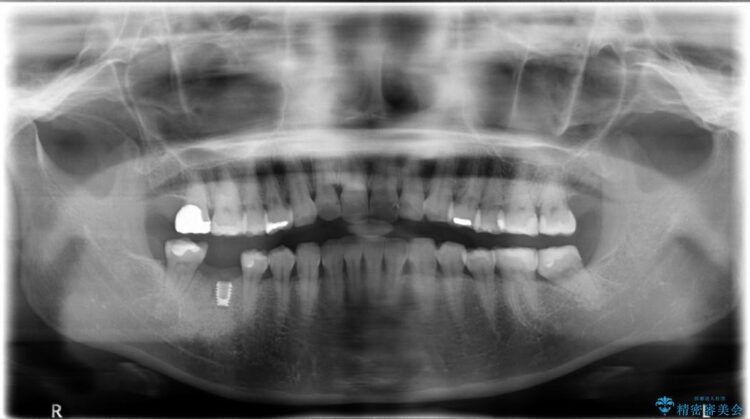

治療後について

抜歯を行った当日に骨の維持をする為、人工の骨を充填しました。インプラントを埋入する際には、ほとんどが自分の骨に置き換わっており、頬舌的なへこみを引き起こす事もなく、審美性・機能性ともに維持する事が出来ました。

また今回の治療では「バイコンインプラント」を使用する事により、インプラントの土台とセラミッククラウンを付ける際にセメントが全く残らないという利点を生かしたところ、見た目にも綺麗に仕上がり、患者様にも喜んでいただきました。